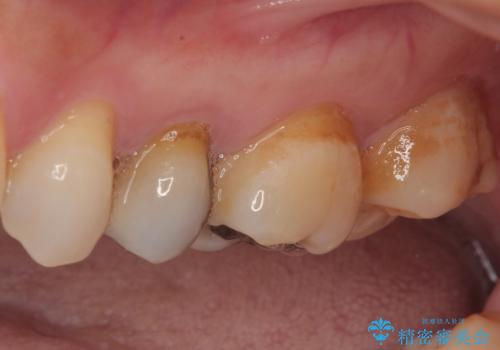

オールセラミッククラウンによる奥歯のむし歯治療

やはりむし歯は大きく、一部歯髄を切除することとなりましたが、その後は良好な経過をたどっています。